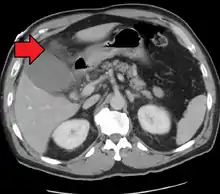

Acute cholecystitis as seen on CT. Note the fat stranding around the enlarged gallbladder.

Right upper quadrant abdominal ultrasound is most commonly used to diagnose cholecystitis.[1][26][27] Ultrasound findings suggestive of acute cholecystitis include gallstones, pericholecystic fluid (fluid surrounding the gallbladder), gallbladder wall thickening (wall thickness over 3 mm),[28] dilation of the bile duct, and sonographic Murphy's sign.[13] Given its higher sensitivity, hepatic iminodiacetic acid (HIDA) scan can be used if ultrasound is not diagnostic.[13][14] CT scan may also be used if complications such as perforation or gangrene are suspected.[14]